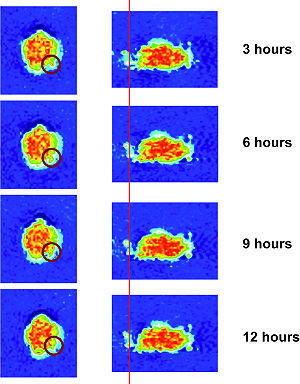

Treatment Planning and Delivery of Whole Brain Irradiation with Hippocampal Avoidance in Rats

Publication: PLoS One. 2015 Dec 4;10(12):e0143208. PMID: 26636762 | PDF Authors: Cramer CK, Yoon SW, Reinsvold M, Joo KM, Norris H, Hood RC, Adamson JD, Klein RC, Kirsch DG, Oldham M. Institution: Department of Radiation Oncology, Duke University Medical Center, Durham, NC, USA. Background/Purpose: Despite the clinical benefit of whole brain radiotherapy (WBRT), patients and physicians are concerned by the long-term impact on cognitive functioning. Many studies investigating the molecular and cellular impact of WBRT have used rodent models. However, there has not been a rodent protocol comparable to the recently reported Radiation Therapy Oncology Group (RTOG) protocol for WBRT with hippocampal avoidance (HA) which is intended to spare cognitive function. The aim of this study was to develop a hippocampal-sparing WBRT protocol in Wistar rats. Methods: The technical and clinical challenges encountered in hippocampal sparing during rat WBRT are substantial. Three key challenges were identified: hippocampal localization, treatment planning, and treatment localization. Hippocampal localization was achieved with sophisticated imaging techniques requiring deformable registration of a rat MRI atlas with a high resolution MRI followed by fusion via rigid registration to a CBCT. Treatment planning employed a Monte Carlo dose calculation in SmART-Plan and creation of 0.5 cm thick lead blocks custom-shaped to match DRR projections. Treatment localization necessitated the on-board image-guidance capability of the XRAD C225Cx micro-CT/micro-irradiator (Precision X-Ray). Treatment was accomplished with opposed lateral fields with 225 KVp X-rays at a current of 13mA filtered through 0.3 mm of copper using a 40x40 mm square collimator and the lead blocks. A single fraction of 4Gy was delivered (2Gy per lateral field) with a 41 second beam on time per field at a dose rate of 304.5 cGy/min. Dosimetric verification of hippocampal sparing was performed using radiochromic film. In vivo verification of HA was performed after delivery of a single 4Gy fraction either with or without HA using γ-H2Ax staining of tissue sections from the brain to quantify the amount of DNA damage in rats treated with HA, WBRT, or sham-irradiated (negative controls). Results: The mean dose delivered to radiochromic film beneath the hippocampal block was 0.52Gy compared to 3.93Gy without the block, indicating an 87% reduction in the dose delivered to the hippocampus. This difference was consistent with doses predicted by Monte Carlo dose calculation. The Dose Volume Histogram (DVH) generated via Monte Carlo simulation showed an underdose of the target volume (brain minus hippocampus) with 50% of the target volume receiving 100% of the prescription isodose as a result of the lateral blocking techniques sparing some midline thalamic and subcortical tissue. Staining of brain sections with anti-phospho-Histone H2A.X (reflecting double-strand DNA breaks) demonstrated that this treatment protocol limited radiation dose to the hippocampus in vivo. The mean signal intensity from γ-H2Ax staining in the cortex was not significantly different from the signal intensity in the cortex of rats treated with WBRT (5.40 v. 5.75, P = 0.32). In contrast, the signal intensity in the hippocampus of rats treated with HA was significantly lower than rats treated with WBRT (4.55 v. 6.93, P = 0.012). Conclusion: Despite the challenges of planning conformal treatments for small volumes in rodents, our dosimetric and in vivo data show that WBRT with HA is feasible in rats. This study provides a useful platform for further application and refinement of the technique. Funding:

|

MRI with labeled structures from atlas registered to the CBCT. Registration was carried out with the open source imaging tool 3D Slicer, Version 4.4.0. |